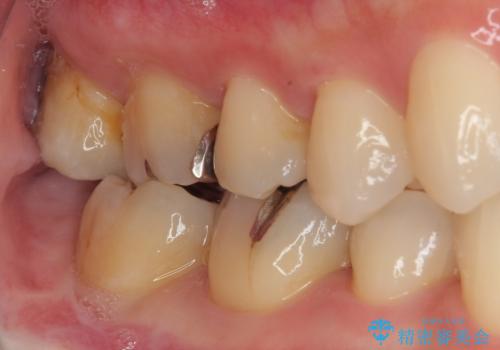

- 元々むし歯があったものの、処置が困難とのことでしたが、矯正治療を終えたので処置をしたいとのことで来院された患者様です。

左右ともに最後臼歯が頬側に顕著に突出しており、むし歯になってしまったことが想像されました。

矯正治療により処置が可能な位置に歯が移動したため、オールセラミッククラウンにて補綴治療を行うこととしました。

歯列が移動したとはいえ、左右ともに後方傾斜しており、むし歯の除去、形成(形を整える)、型取りの全てが非常に困難な処置となりました。